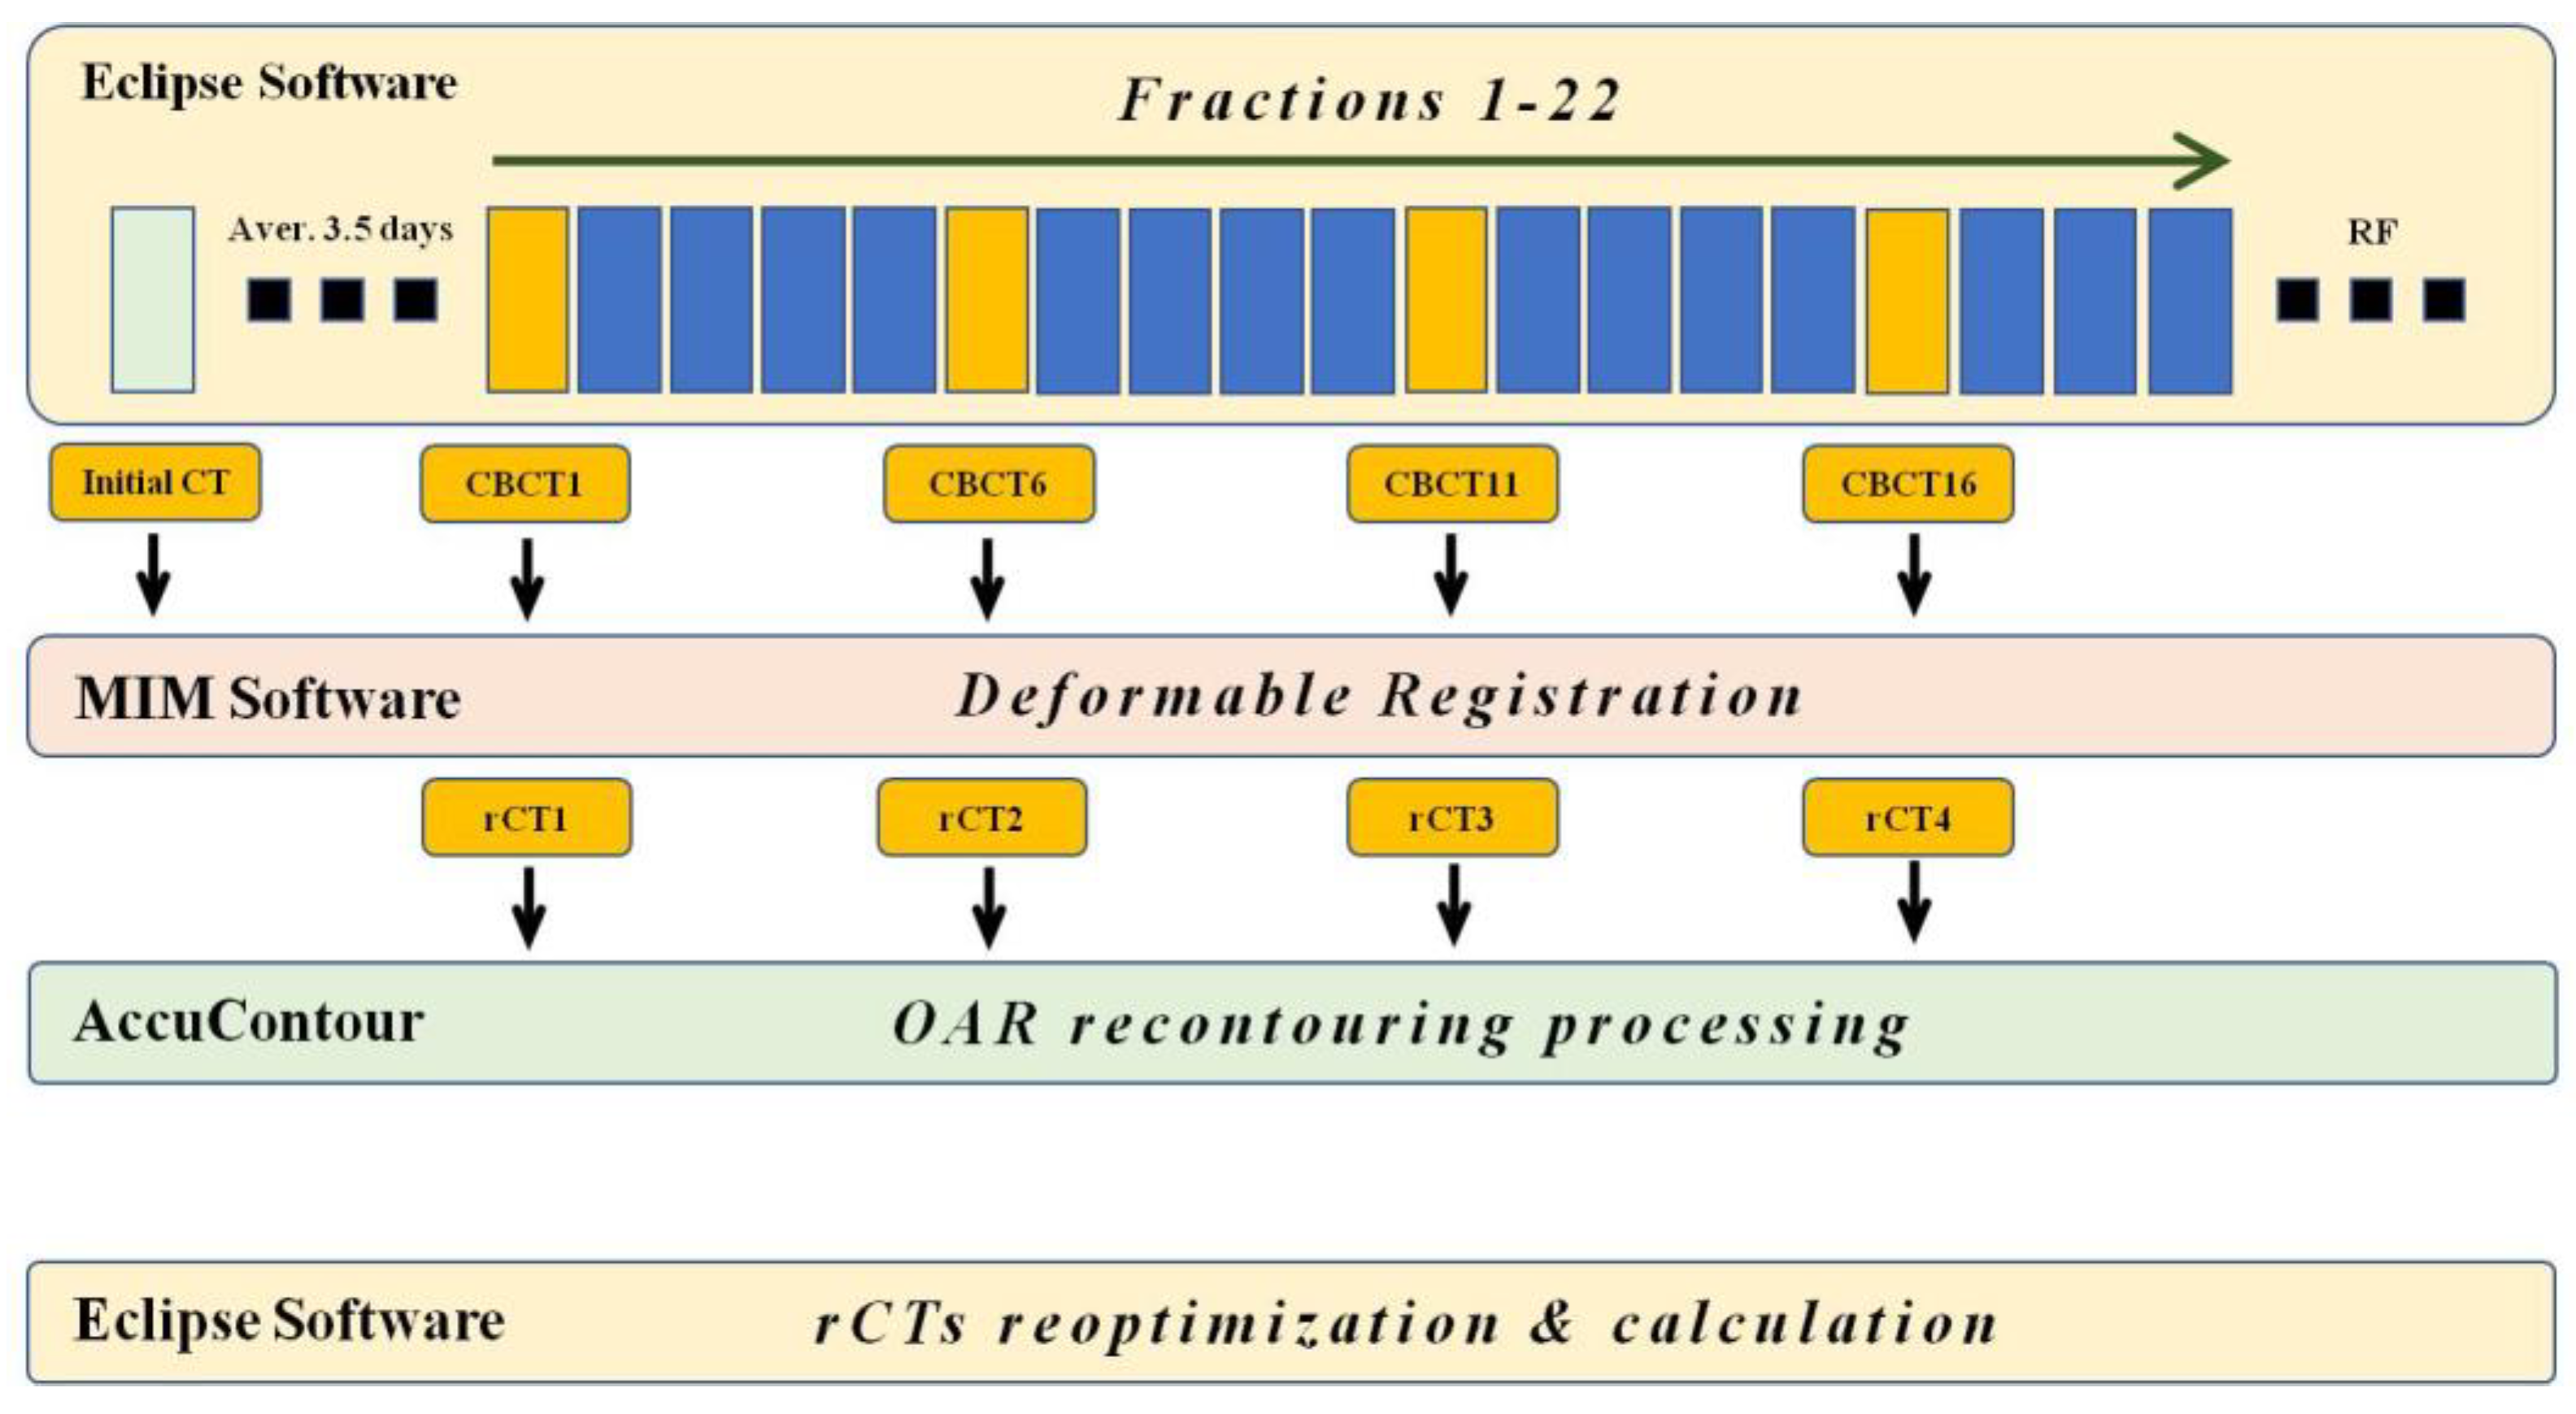

2.2. Patient Simulation and Treatment Planning Process

2.3. Imaging Acquisition and Registration Process

2.4. Treatment Plan Application and Recalculation